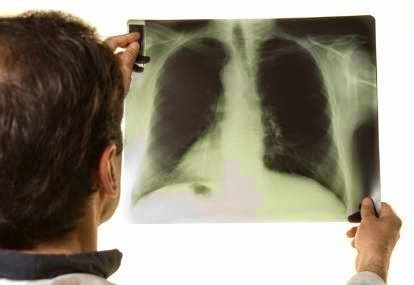

Obat tumor paru-paru secara alami ~ Penyakit tumor bisa tumbuh dimana saja termasuk pada organ pernapasan paru-paru. Penyakit tumor paru-paru adalah penyakit dengan ciri khas adanya pertumbuhan sel yang tidak terkontrol pada jaringan paru-paru. Pertumbuhan penyakit ini akan berkembang keluar dari paru-paru melalui suatu proses bernama metastasis jika tanpa adanya perawatan.

Gejala penyakit tumor paru-paru

Kanker paru-paru yang dini tidak menunjukkan gejala. Namun, seiring

pertumbuhan kanker tersebut, beberapa gejala umumnya meliputi:

- Batuk yang memburuk dan tidak pernah sembuh

- Kesulitan bernafas, seperti kehabisan nafas / sesak nafas

- Sakit di dada secara konstan

- Batuk darah

- Suara yang serak

- Sering terkena infeksi paru, seperti pneumonia

- Merasa letih setiap saat

- Kehilangan berat badan tanpa sebab yang jelas